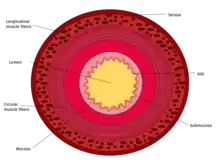

The three sections of the small intestine look similar to each other at a microscopic level, but there are some important differences. The parts of the intestine are as follows:

| Layer | Duodenum | Jejunum | Ileum |

|---|---|---|---|

| Serosa | 1st part serosa, 2nd–4th adventitia | Normal | Normal |

| Muscularis externa | Longitudinal and circular layers, with Auerbach's (myenteric) plexus in between | Same as duodenum | Same as duodenum |

| Submucosa | Brunner's glands and Meissner's (submucosal) plexus | No BG | No BG |

| Mucosa: muscularis mucosae | Normal | Normal | Normal |

| Mucosa: lamina propria | No PP | No PP | Peyer's patches |

| Mucosa: intestinal epithelium | Simple columnar. Contains goblet cells, Paneth cells | Similar to duodenum, but the intestinal villus is long | Similar to duodenum, but the intestinal villus is short |

Tissue layers (mucosa, submucosa and muscularis)